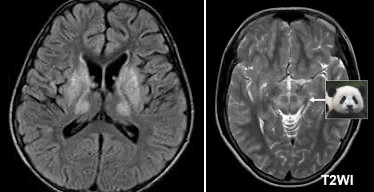

• 영상 소견

• T2/FLAIR: GP, thalamus, midbrain 의 High SI